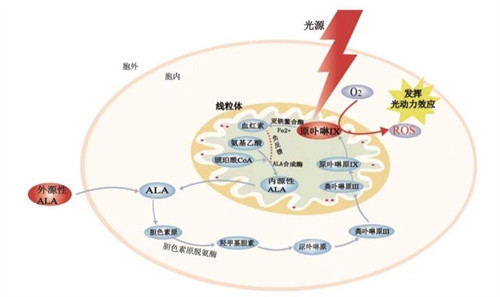

首可靠行玻璃体切除,清除眼内玻璃体以提供清晰视野;随后使用特定染色剂(如亮蓝)使黄斑前膜显色,便于比较准操作。

在显微镜下,医生用精细工具(如视网膜钩或镊子)小心抓住并剥离前膜,尽量减少对视网膜的损伤。